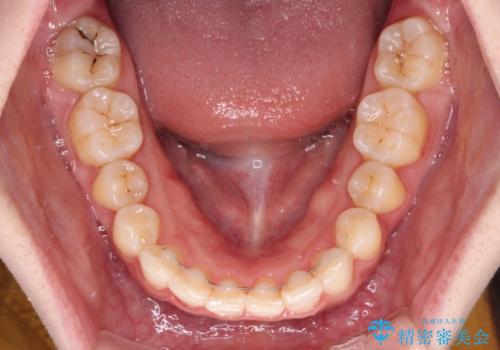

半年もせずにインビザラインを全く使用することができなくなってしまったので、治療開始から1年ほどでワイヤー矯正へ変更することとなりました。

ワイヤー矯正へ変更してからはあっという間に治療が進み、1年弱で終えることができました。